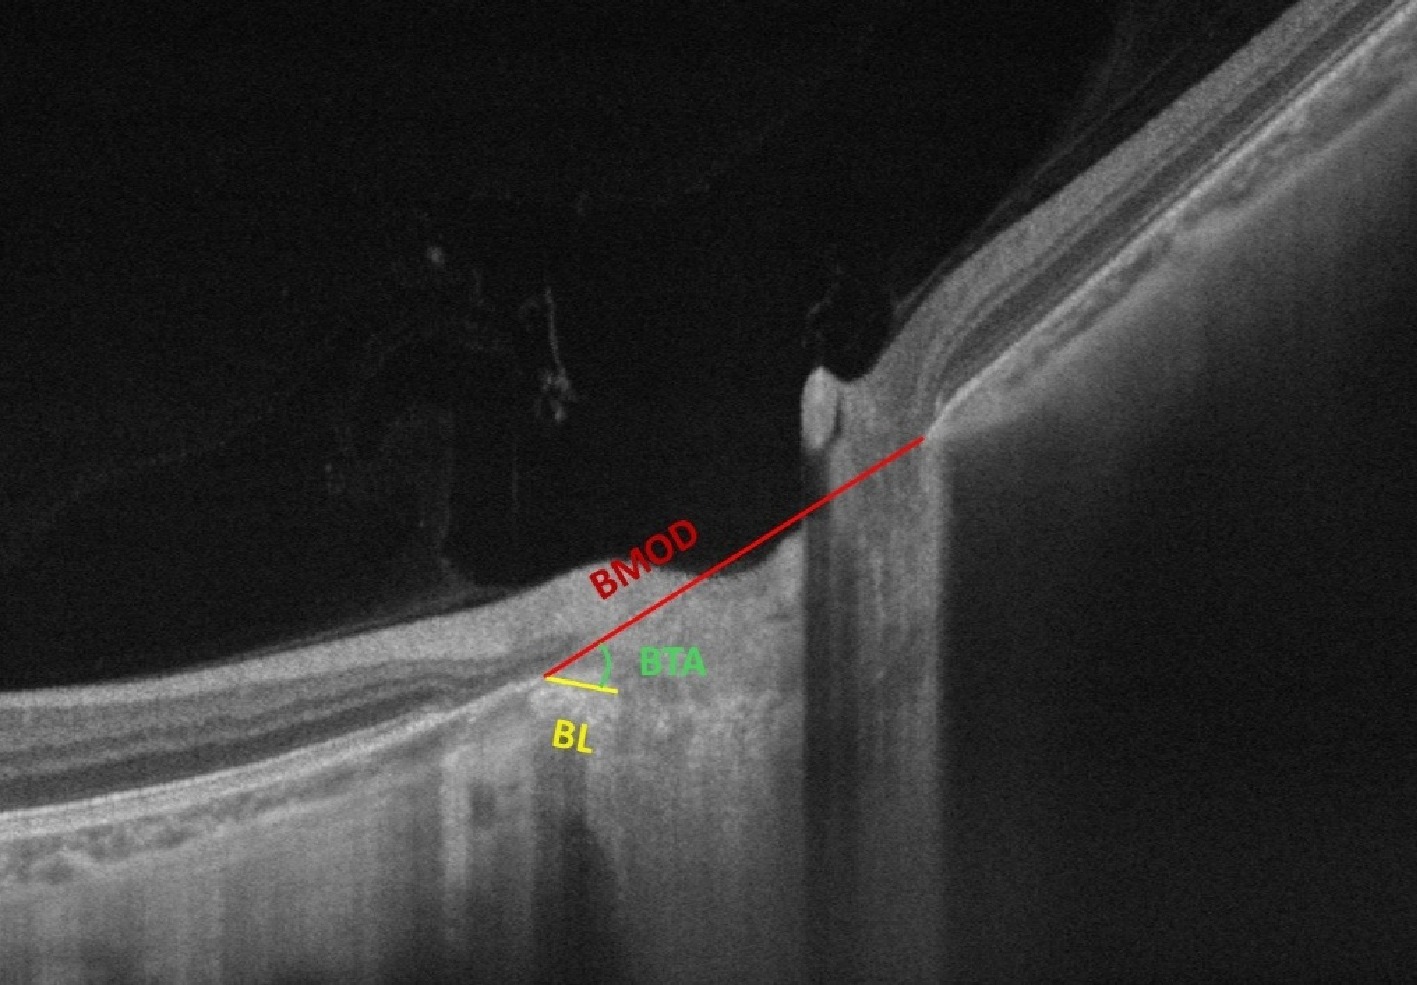

In addition to parapapillary zones, several studies have investigated ultrastructural changes related to BM in high myopia, including Bruch's membrane opening distance (BMOD), border length (BL), border tissue angle (BTA), focal LC defects, and peripapillary intrachoroidal cavitation (PICC) (Fig. 3). The BMOD is defined as the distance between the two points of the BMO on a horizontal B-scan, taken across the midpoint of the optic disc's longest axis. The BL refers to the straight-line distance from the temporal BMO point to the border tissue and the scleral termination. The BTA is defined as the angle formed between the reference plane of the BMO and the border tissue[33]. Hu et al.[41] found that in young adults aged 16−28 years with high myopia, BMOD and BL were longer, while BTA was smaller. Axial length (AL) was positively correlated with BMOD and BL and negatively correlated with BTA. As myopia progresses, the increase in BMOD and the decrease in BTA precede the expansion of the PPA area and subsequent globe deformation. This suggests that, compared to the PPA, BMOD and BTA were considered earlier indicators of fundus changes in high myopia. In contrast, a study by Kim et al.[42] in children aged 6.7−12.5 years found that during changes in the ONH and PPA, BL increased nasally, and BTA decreased, whereas BMOD remained relatively stable. They suggested that in children, physiological growth might counterbalance rapid axial elongation, and structural changes in BMOD may not be as pronounced at this stage.

Figure 3.

Illustration of Bruch's membrane opening distance (BMOD), border length (BL), and border tissue angle (BTA) in optical coherence tomography. BMOD refers to the distance between the two points of the Bruch's membrane opening (BMO) on a horizontal B-scan; BL refers to the straight-line distance from the temporal BMO point to the border tissue and the scleral termination; BTA refers to the angle formed between the BMOD line and the BL line. (Source: Personal fundus images provided by Mr. Jinze Zhang, Sun Yat-sen University).